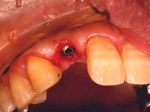

二次オペ時

仮の支柱を装着